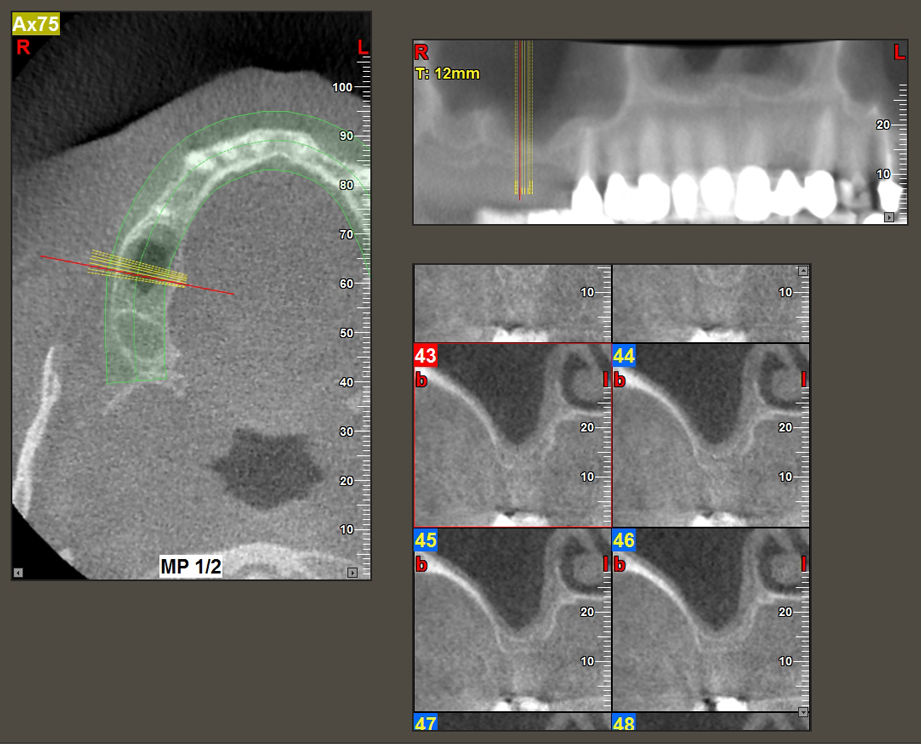

Une patiente de 49 ans, non fumeuse et sans antécédents médicaux remarquables, a été orientée vers notre cabinet de chirurgie orale pour l’extraction chirurgicale de la dent 16 préalable à la pose d’un implant. Après l’extraction, la patiente a rencontré de légers problèmes de sinusite, à la suite de quoi nous avons commencé par attendre six mois avant de prendre la mesure. À l’endroit prévu pour la pose de l’implant, l’os résiduel mesurait 3-4 mm de haut (Fig. 1 et 2).

Fig.2 : La DVT montre des dimensions adéquates sur chacune des vues axiale (gauche), latérale (dessus) et transversale (droite). La membrane du sinus maxillaire est encore légèrement épaissie.